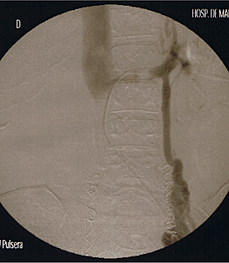

Figure 4 Treatment of pelvic venous congestion by ovarian vein embolization and right internal iliac vein Pelvic congestion syndrome and pelvic varicosities 95. Title: Pelvic Congestion Syndrome and Pelvic Varicosities Author: Sonya Koo Subject: ... Access Content